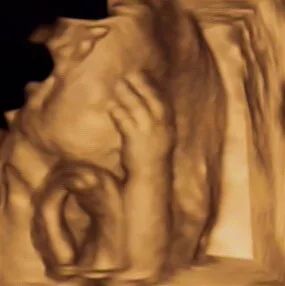

超声影像(四维彩超)的立体成像效果及清晰度,受孕妈胎位情况及宝宝的配合程度而定。

能否与宝宝面对面,这取决于胎宝宝在做超声那会儿的身体姿势,如果胎宝宝正面对你,并且五官周围羊水很充足,那简直是太幸运了,能看到清晰的五官。

但是如果胎宝宝正好脸背着你,或者脸部周围羊水不多,胎宝宝因皮肤呈皱褶状态,还有一层胎脂保护着宝宝,在超声采集相片时,会影响图片的清晰度。还有一部分胎宝宝的头部位置比较低,头在骨盆内,孕妈骨盆的骨骼会干扰我们的四维仪器,导致胎宝宝面部图像模糊。